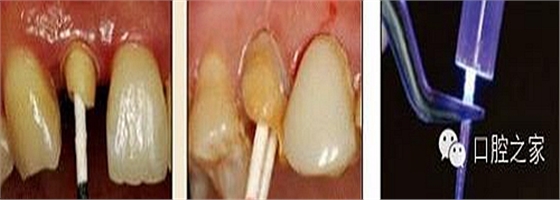

11. 吸取根管內(nèi)多余的粘結(jié)劑

根管內(nèi)涂抹粘接劑時,理想的粘接劑層厚度應(yīng)為25μm~40μm,厚度增加或不均勻不僅導(dǎo)致粘接強度的下降,也不利于纖維樁在根管內(nèi)的暢通就位。其次,多余粘接劑的存在往往會加速樹脂水門汀的固化速度,使纖維樁無法及時就位而導(dǎo)致粘接失敗。根管內(nèi)涂抹粘接劑較規(guī)范的操作應(yīng)該是,毛刷蘸取粘接劑在根管內(nèi)反復(fù)涂擦20s,涂抹2-3層(圖 22),然后用紙尖吸取干凈(圖 23),氣槍吹 5s使粘接劑中的溶劑快速揮發(fā)。在該操作步驟中,大錐度紙尖的應(yīng)用非常關(guān)鍵,也往往被很多醫(yī)生忽視,它不僅可以吸取多余粘接劑,同時也可使粘接劑在根管內(nèi)鋪展均勻。

圖22:粘接劑涂擦20s,涂抹2-3層。 圖23:紙尖吸出多余粘接劑。